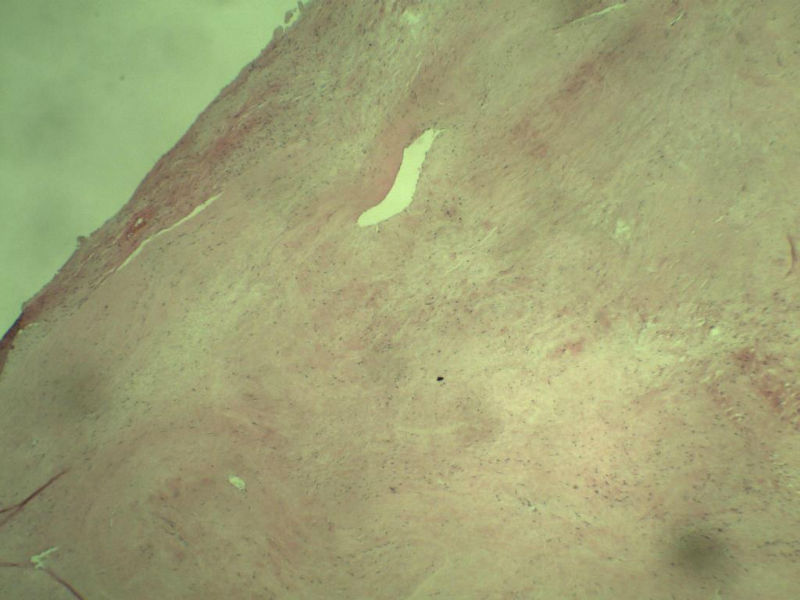

男,51岁, 4月前患者无意中发现右腘窝一包块,约核仁大小无疼痛, 4月来包块进行性生长

灰褐类圆形包块一个,直径 5 cm,切面灰白,实性,编织状。 请各位老师看看 是什么? 谢谢!